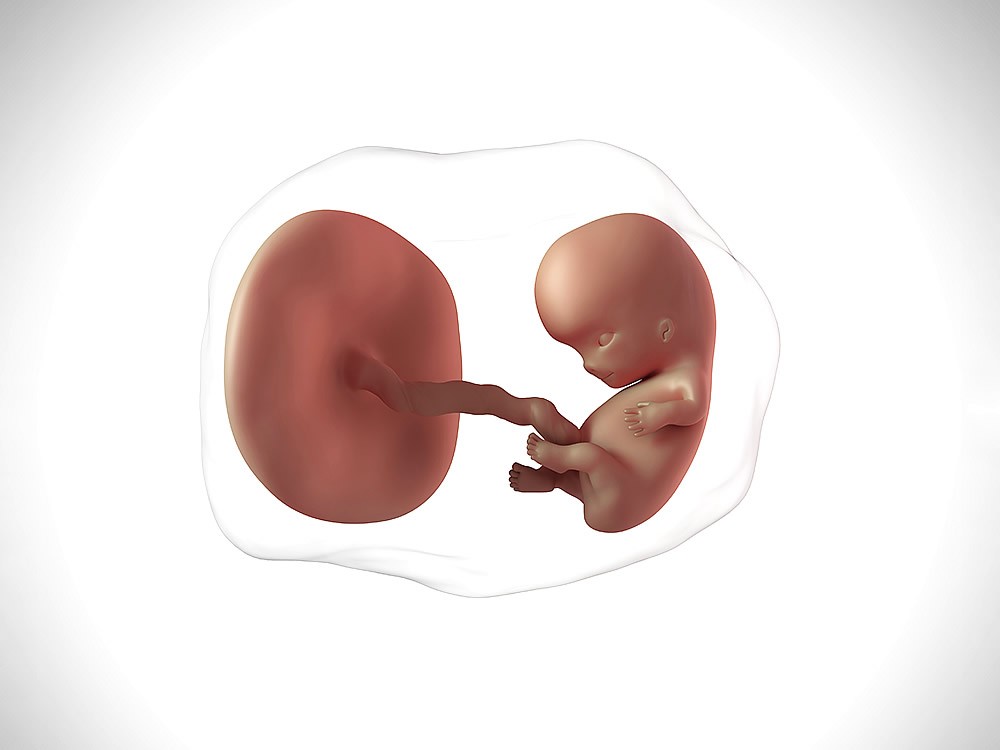

Kilosu da artık 1000 grama ulaşmıştır. Canim sanirim ilk baslarda cok hissedilip biraz zaman gectikten sonra azalmasi normal. Hareketlerin azalması bebeğin sıkıntıda olduğunu düşündürür ve ileri tetkik gerektirebilir.

Yağ katmanlarını da koyduğunda, bebek şimdi baştan ayağa yaklaşık 37,6 cm boyunda ve yaklaşık 1,1 kg ağırlığında. Bu nedenle hareketlerinin azalması sizleri endişeye sürüklemesin. 28 haftalık gebelik bebek hareketleri konusunda belirleyici bebek hareketlerinin de görüldüğü haftadır.

Kilosu da artık 1000 grama ulaşmıştır. Bunun nedeni rahim içindeki boşluğun küçülmesidir. Bebek hareketlerinin azalması pek çok anne adayında tespit edilmektedir ve bu vakaların bir kısmında bebeğin ciddi bir hayati tehlike altında olması da muhtemeldir.